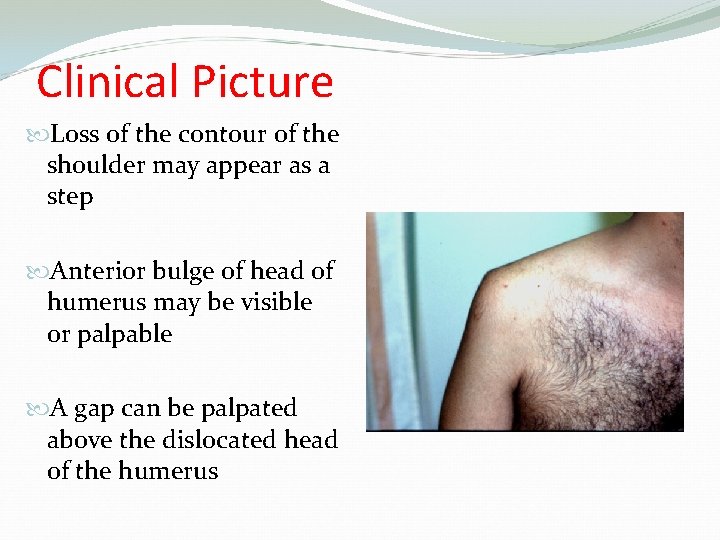

Clinical Picture Loss of the contour of the shoulder may appear as a step Anterior bulge of head of humerus may be visible or palpable A gap can be palpated above the dislocated head of the humerus